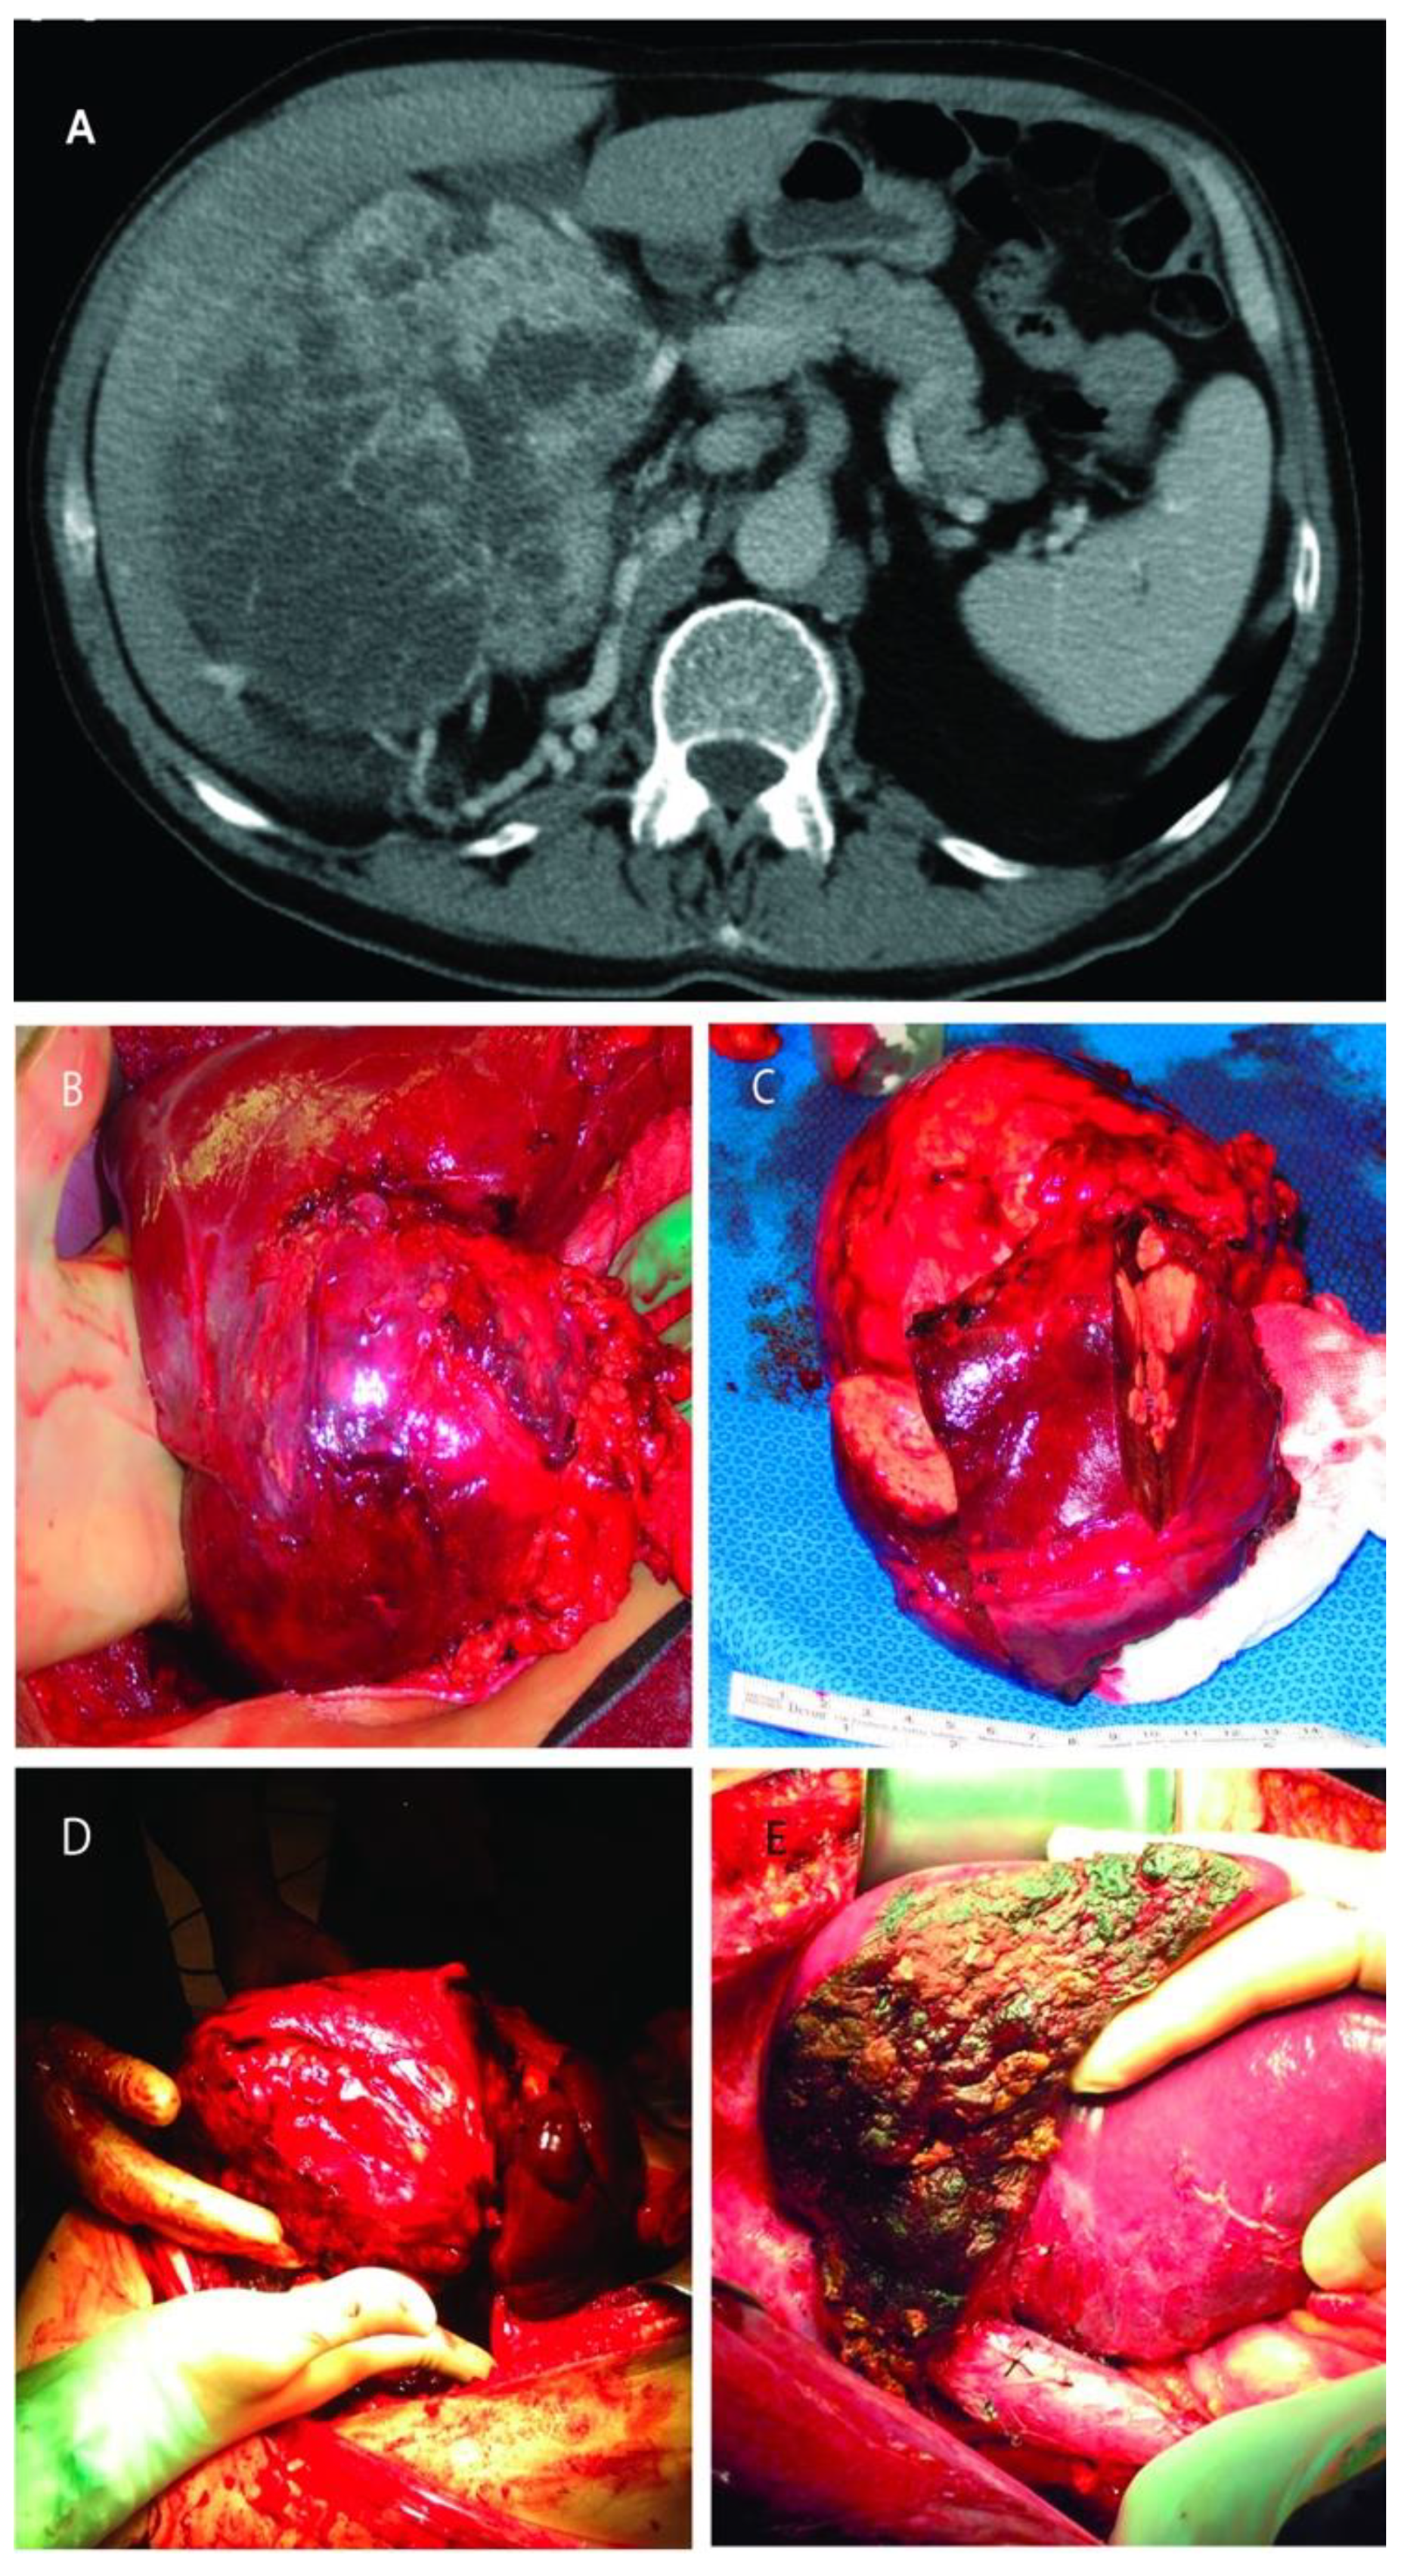

RCC was infiltrating the right lobe in three patients. Partial right lobectomy was performed en-bloc with the renal tumor and adrenal gland in three patients, resection of segments two and three in one patient, and wedge-resection of the liver mass in other three patients. Four of these patients harbored also an IVC tumor thrombus (level I in n = 3, and level II in n = 1) that required additional thrombectomy, tangential cavectomy, and primary closure. Of note, one of the patients that underwent a partial right lobectomy had two previous unsuccessful ipsilateral renal artery embolization attempts complicated by massive bleeding before referred to our institution (Figure 3).

Figure 3.

(A): Computed tomography of large right renal mass with collaterals from the liver; (B): Right renal mass with renal artery and vein ligated but still with blood flow from the liver; (C): The resected specimens of right renal mass with right lobe of the liver; (D): Right renal mass infiltrating the right lobe of the liver; (E): Remaining liver after almost complete right lobectomy.